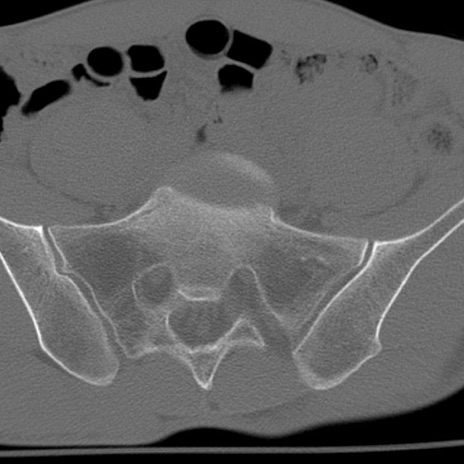

症例3 腰椎CT(横断像)

腰椎CT